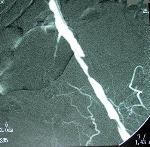

Perkutánní transluminální angioplastika (PTA) + zavedení stentu pánve a dolních končetin

PTA se provádí v místním znecitlivění a je to výkon nebolestivý. Do tepny obvykle v třísle se zavede jehla, přes kterou zavedeme vodič a kterým pronikneme skrz postiženou oblast až do „zdravé“ tepny. Poté do postižené oblasti zavedeme speciální balonkový dilatační katetr (balónek) a „nemocnou“ tepnu ošetříme buď pouze roztažením balonku nebo zavedením stentu, který drží požadovaný průměr ošetřované tepny. Současně se získávají snímky léčené oblasti před a po léčbě pomocí PTA. Na konci výkonu lékař odstraní zaváděcí pouzdro, balonek a vodič (instrumentárium) a místo, kudy bylo instrumentárium zavedeno se stlačí na dobu nezbytně nutnou k zástavě krvácení z tepny. Délka výkonu je zcela individuální v závislosti na lokalizaci a závažnosti postižení tepenného systému. Délku výkonu upřesní výkon provádějící intervenční radiolog.